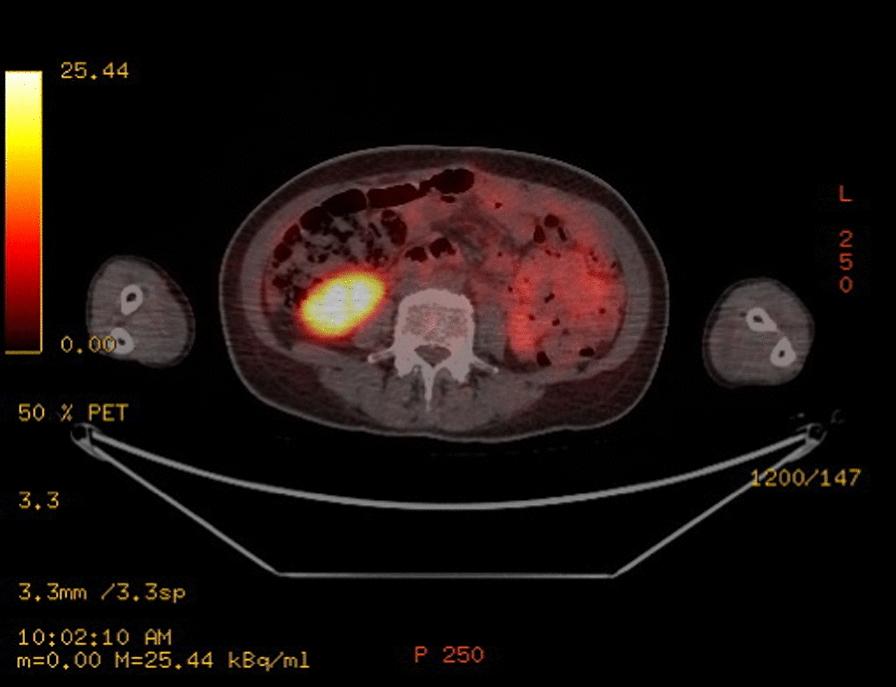

We are reporting a case of primary ovarian neuroendocrine neoplasm in association with an epithelial borderline tumor. She is a 50-year-old Filipino woman who presented with nonspecific symptoms. Initial imaging revealed a large mass with suspicion of widespread metastasis. However, further imaging and laparotomy revealed early-stage neuroendocrine neoplasm, a large borderline epithelial tumor, with no evidence of pulmonary metastasis, despite having pleural effusion. She was lost to follow-up, presented again after a year with evidence of residual disease/metastasis, and was treated with chemotherapy.

我们报告一例原发性卵巢神经内分泌肿瘤合并上皮性交界性肿瘤的病例。患者为一名50岁的菲律宾女性,出现非特异性症状。初始影像学检查发现一个大肿块,怀疑有广泛转移。然而,进一步的影像学检查和剖腹手术显示为早期神经内分泌肿瘤,一个大的交界性上皮性肿瘤,尽管有胸腔积液,但无肺转移证据。她失访了,一年后再次就诊,有残留疾病/转移的证据,并接受了化疗。